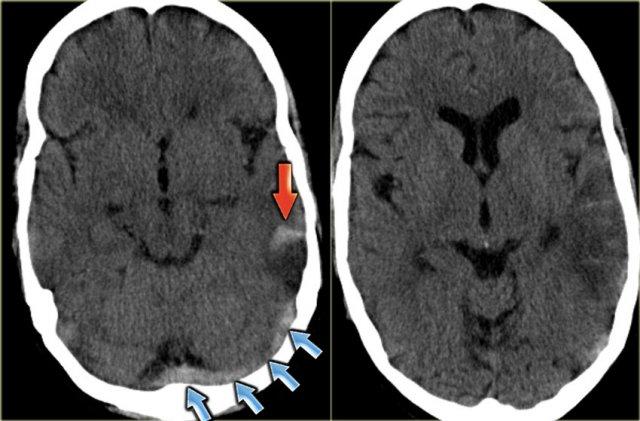

Bên trái là hình ảnh xoang ngang có huyết khối và bên cạnh là xoang ngang bình thường.

Ở trẻ nhũ nhi, nhu mô não thường có tỷ trọng thấp hơn so với trẻ lớn và người trưởng thành.

Điều này dẫn đến tỷ trọng tương đối cao của máu trong xoang dọc trên so với nhu mô não, tạo ra hình ảnh giả dấu hiệu cục máu đông tăng tỷ trọng.

Đây là hình ảnh một bệnh nhân có khối máu tụ trong não ở vị trí ngoại vi.

Do vị trí của khối máu tụ nằm trong vùng xoang ngang, nó tạo ra hình ảnh giả xoang ngang có huyết khối.

Đây là hình ảnh một bệnh nhân có khối máu tụ dưới màng cứng bên trái, lan rộng đến vùng xoang dọc trên (các mũi tên).

Thoạt nhìn, hình ảnh này trông giống như dấu hiệu delta rỗng.

Khi duyệt qua toàn bộ tập dữ liệu, có thể thấy rõ đây là phần lan rộng của khối máu tụ.

Bên trái là ba hình ảnh của một bệnh nhân có huyết khối tĩnh mạch tại xoang dọc trên.

Ở hình ngoài cùng bên trái, chúng ta thấy dấu hiệu mạch máu tăng tỷ trọng trên CT không tiêm thuốc cản quang.

Hình ở giữa được chụp 25 giây sau khi bắt đầu tiêm thuốc cản quang.

Có hình ảnh ngấm thuốc động mạch và trông như thể xoang dọc trên cũng đang ngấm thuốc, nhưng thực chất đây là hiện tượng “xuyên sáng” (shine through) của cục huyết khối tăng tỷ trọng.

Chỉ đến hình ảnh bên phải, được chụp 45 giây sau khi tiêm thuốc cản quang, mới xuất hiện dấu hiệu delta rỗng, xác nhận sự hiện diện của huyết khối trong xoang.